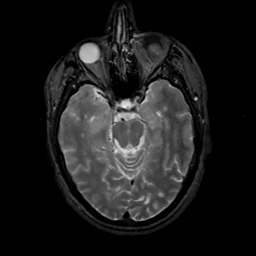

MR Study #7, March 24, 1991 -- Slice #18